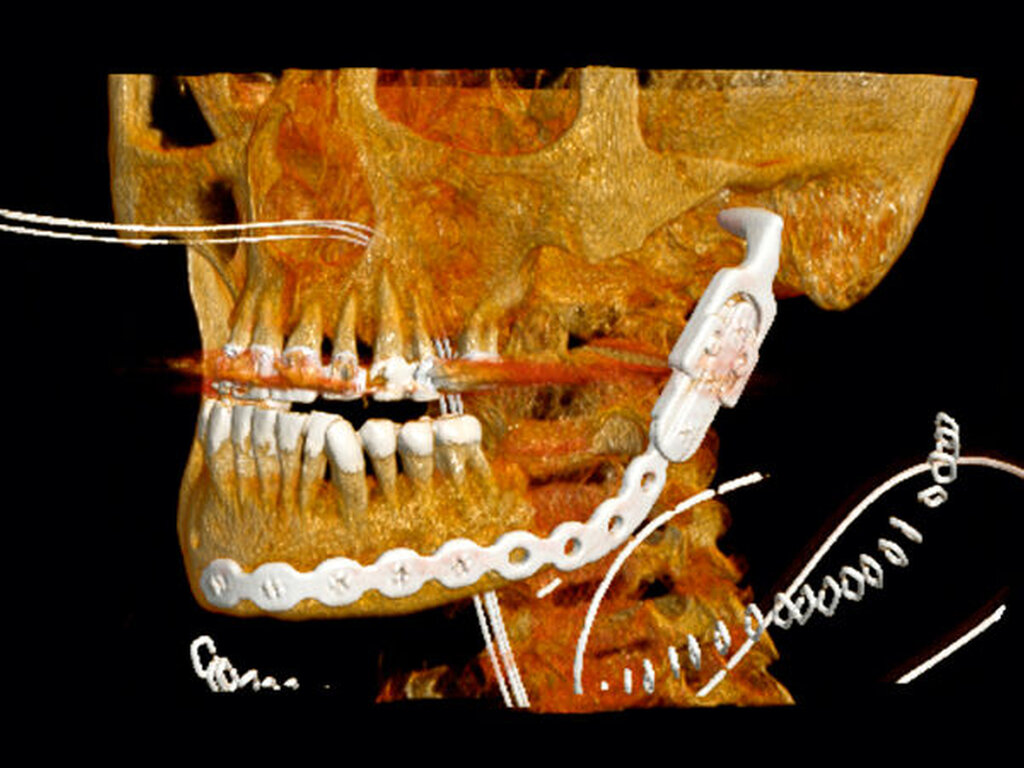

Aufgrund des ausgedehnten Befunds fiel die Entscheidung zu einer Kontinuitätsresektion mit einer Exartikulation des linken Kiefergelenks und Einbringen einer Rekonstruktionsplatte mit Gelenkersatz (Abbildung 4). Der N. alveolaris inferior sowie der N. lingualis konnten erhalten werden. Die pathologische Aufarbeitung des Unterkieferresektats zeigte eine umschriebene Knochennekrose mit mehrherdiger, überwiegend chronischer Osteomyelitis zusammen mit einer Fettmarksfibrose und einer periostalen Stromafibrose.